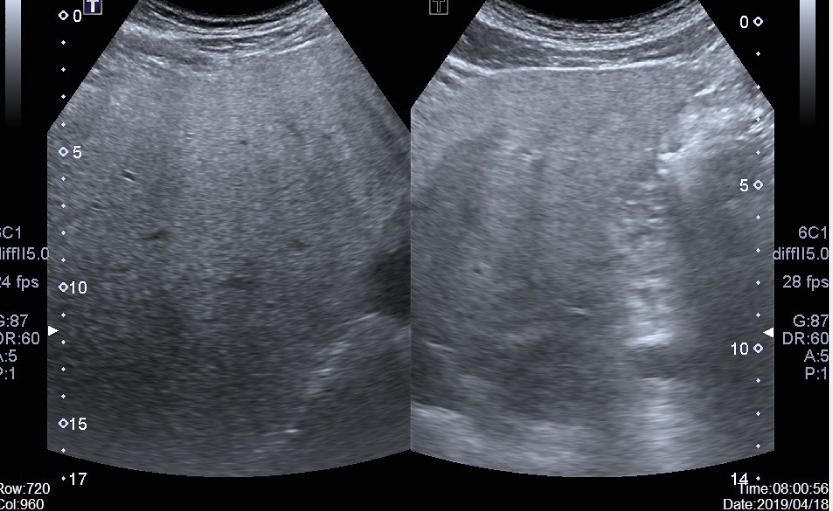

1、 脂肪肝:对于伴有ALT升高的脂肪肝患者,建议适当运动、清淡饮食,随着体重的减轻,ALT会逐渐好转恢复正常。必要时请遵从专业医生建议,酌情加用还原型谷胱甘肽、天晴甘平、益肝灵等保肝药物。